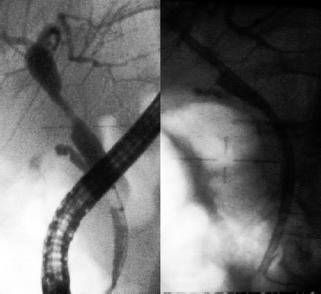

- Anastomotic stenosis: short single lesions located at the site of the anastomosis (Figure 1).

- Non-anastomotic stenosis: multiple lesions which are predominantly hilar, or diffuse intrahepatic lesions (Figure 2).

Figure 1. Single stenosis in a successfully managed anastomosis with successive changes of plastic stents for almost a year.

Figure 2. Endoscopic correlation with an MRI in a patient with long and multiple non- anastomotic stenosis.